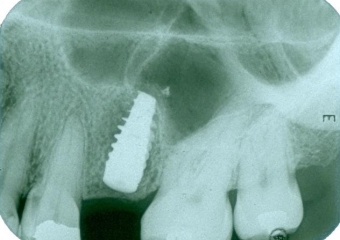

Imagens iniciais com dentes 11 e 25 comprometidos

Raio X inicial